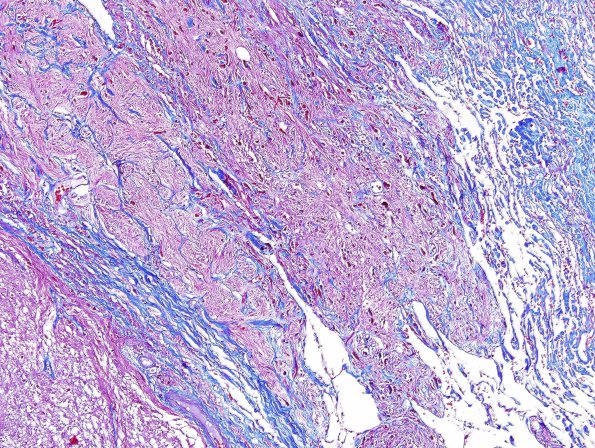

Washington University Experience | NEOPLASMS (GLIAL) | Astrocytoma, pilocytic - Gross Pathology | 7D1 Astrocytoma, pilocytic, optic nerve (Case 7) Trichrome 2.jpg

7D1,2 The portion of the intraneural and intradural sleeve are separated and invaded as shown in this trichrome stain for collagen.